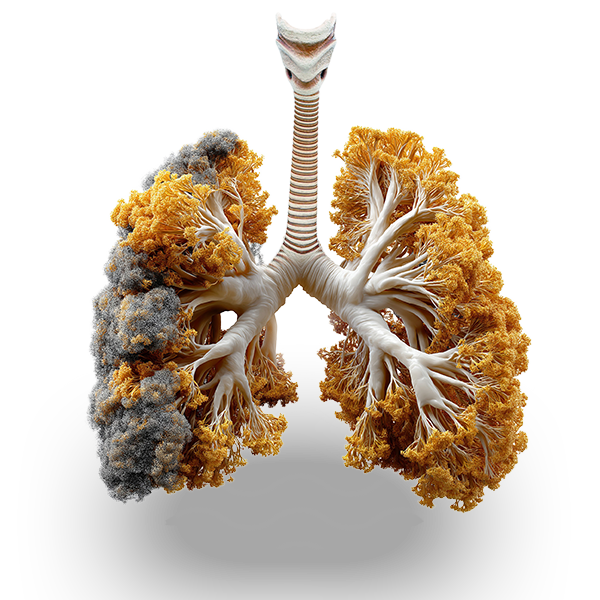

WEAKENED FROM THE INSIDE

Vaping can damage your body’s natural ability to defend itself.

Every day we learn about new ways that vaping can be harmful to our bodies. Studies have found cancer-causing chemicals in vape juice, like pulegone, AND vapor, like formaldehyde.

Inhale at Your Own Risk

Whether you vape THC or nicotine, it doesn’t matter. There’s no such thing as a safe vape. ALL have been associated with serious health risks.

Doctors have seen thousands of vape-related hospitalizations, including severe breathing problems, pneumonia, and over 65 deaths—including a 15-year-old.